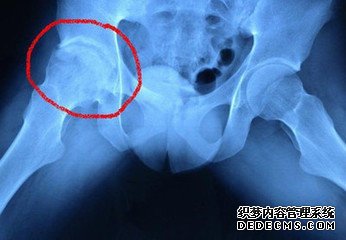

乌兰察布妇科医院专家称,人流常识是骨伤科临床常见而又难治的慢性疾病之一,人流常识是由于髋部外伤、长期应用激素类药物、酒精中毒等原因,引起股骨头血液供应障碍,股骨头骨组织不能得到正常的营养,使股骨头组织中的骨细胞、骨髓造血细胞、脂肪细胞发生坏死。由于坏死的骨组织脆弱,加之髋关节需要负重,日久就会发生股骨头塌陷,影响全部髋关节。一旦出现症状,应及时到医院检查确诊,并采取系统的治疗。

早期常为髋关节附近隐痛钝痛,出现间歇性或持续性疼痛,常向大腿及膝部放射,劳累后情况加重;晚期的疼痛多因股骨头塌陷、破损等情况引起,或是活动时关节内摩擦而疼痛。

早期患者因疼痛或是肌肉痉挛,常呈防痛步态,患侧足刚一踏地便抬起,而健足落地重而时间长,自主性保护状态下出现间歇性跛行;晚期患者股骨头有塌陷,造成双下肢不等长,形成跛行;患肢肌肉萎缩引起跛行。

患髋关节屈伸不利、下蹲困难、不能久站、行走鸭子步。早期主要表现在外展和内旋受限最为明显。晚期患者会有严重髋关节功能障碍。